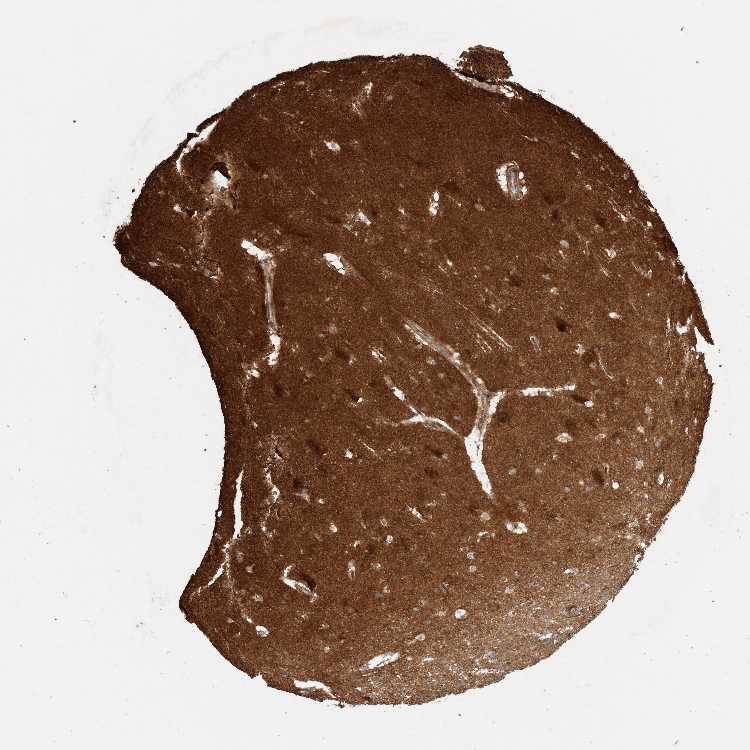

HIPPOCAMPUS - Antibody stainingi

Antibody staining in the annotated cell types in the current human tissue is reported as not detected, low, medium, or high, based on conventional immunohistochemistry profiling in selected tissues. This score is based on the combination of the staining intensity and fraction of stained cells.

Each image is clickable and will lead to virtual microscopy that enables deeper exploration of all samples and also displays staining intensity scores, fraction scores and subcellular localization as well as patient and tissue information for each sample.

Antibody HPA022988Antibody HPA024446

Glial cells Not detectedMedium

Neuronal cells Not detectedHigh